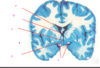

what is A?

infundibulum

falx cerebri

tentorium cerebelli

tentorial notch

falx cerebelli

what is A?

infundibulum

falx cerebri

tentorium cerebelli

tentorial notch

falx cerebelli

which of the following is the lateral ventricle?

A

B

C

D

E

which of the following is the lateral ventricle?

A

B

C

D

E